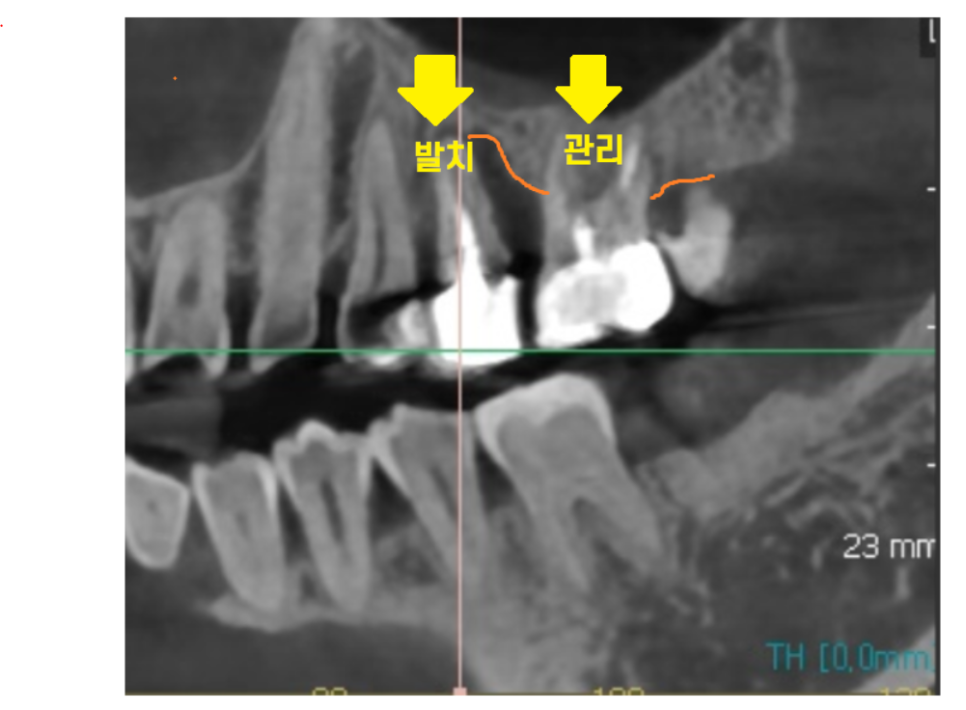

이밖에도..ct도 적극적으로 활용하는데요.

221214

남아 있는 치아의 수명을 결정할 때

도움이 되기 때문입니다.